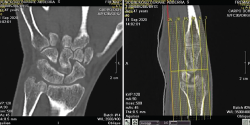

Figura 4. Clasificación de Minnaar de las coaliciones del carpo.

Clasificación de Minnaar de las coaliciones del carpo (Figura 4)

- Tipo I: fusión incompleta con apariencia de pseudoartrosis.

- Tipo II: completa solo por uno de los bordes de unión entre ambos huesos.

- Tipo III: fusión completa.

- Tipo IV: completa asociada a otras anomalías del carpo.

De todas ellas, la más frecuentemente encontrada fue el tipo III, que representa el 46,8%.